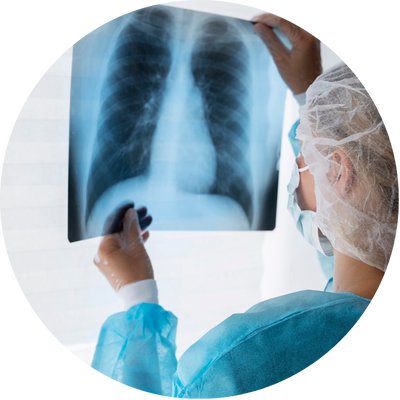

Raio X

Raio X: Diagnósticos Precisos e Confiáveis com Tecnologia Avançada para Sua Saúde